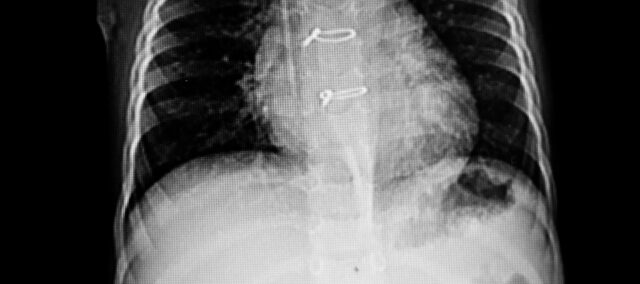

Primárnym výsledkom bola separácia sterna meraná pomocou ultrazvuku. Kvantifikovala sa vzdialenosť medzi oboma polovicami hrudnej kosti a označil sa bod najväčšieho oddelenia. Ako sekundárny výsledok sa použila stupnica nestability sterna, ktorá hodnotí integritu sterna od stupňa 0 (klinicky stabilné sternum) po stupeň 3 (výrazný pohyb alebo oddelenie). Merania sa uskutočnili na začiatku (7. deň po operácii) a v 4. týždni.

Do štúdie bolo zaradených 36 žien, u ktorých bola ultrazvukom potvrdená akútna nestabilita hrudnej kosti. Základné charakteristiky ukázali dve porovnateľné skupiny. Ich základná hrudná vzdialenosť bola 0,23 cm

Primárny výsledok separácie sterna v 4. týždni bol 0,13 cm v experimentálnej skupine a 0,22 cm v kontrolnej skupine. Tým sa dosiahol rozdiel medzi skupinami -0,09 cm (95 % CI 0,07 až 0,11) v prospech intervenčnej skupiny vykonávajúcej stabilizačné cvičenia trupu po sternotómii.